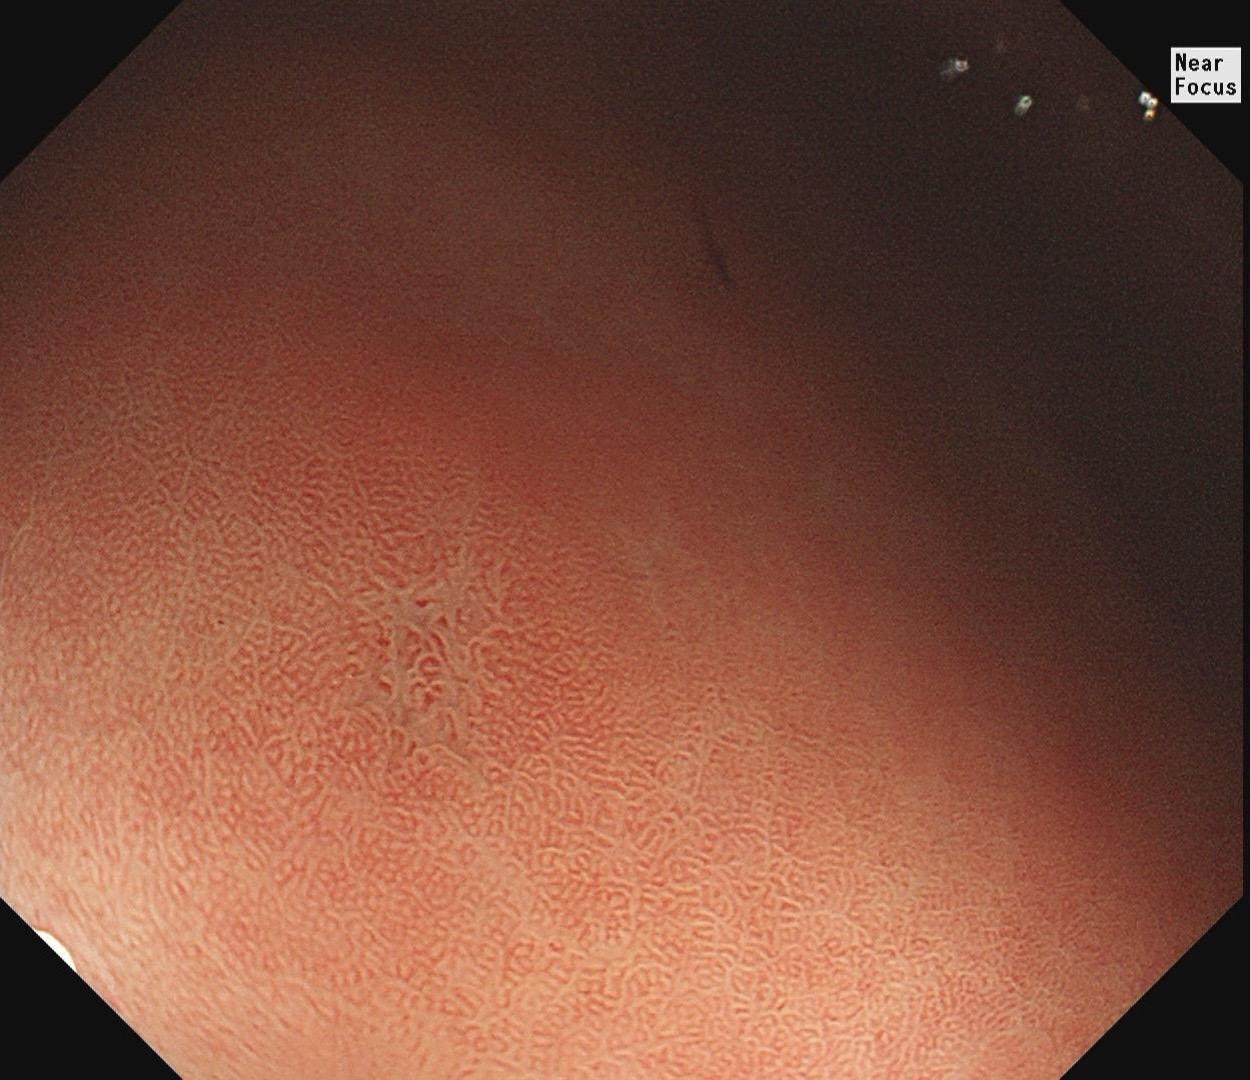

小小的糜烂一枚。这样的病灶,就算结果是阴性的,也很有意义~